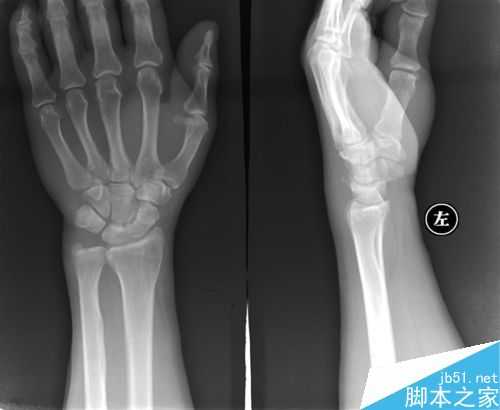

6、警惕鼠标手,严重必须手术

鼠标手是一种病程很长的疾病。前期的鼠标手可以自愈,如果得了鼠标手却满不在乎,那么拖到后期了,就会变成一种顽症,想要彻底治愈,只能通过手术的方式了。